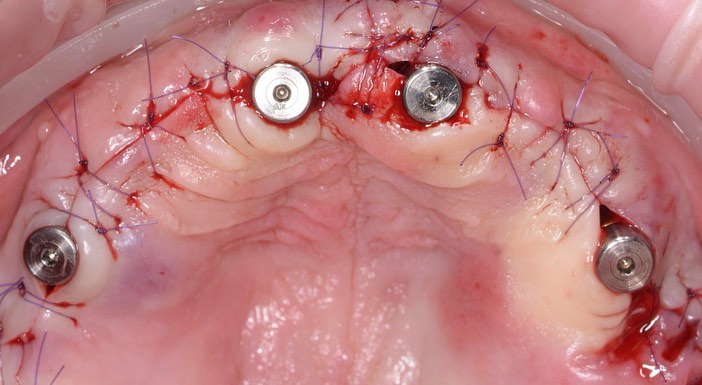

Тотальная имплантация AnyOne методом all-on- 4.

Иващенко Александр Николаевич: клинический стоматолог-хирург, практикующий имплантолог.